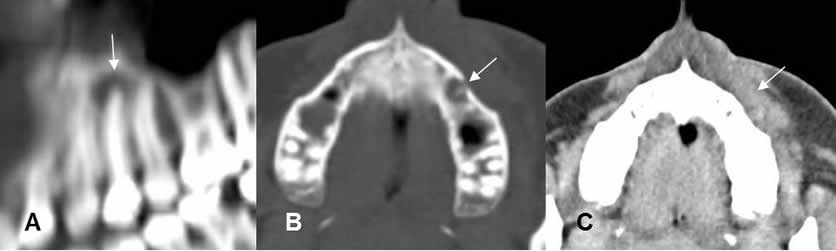

Fig 38. Enfermedad endodental.

A: TAC axial, B: TAC reconstrucción coronal y C: TAC reconstrucción sagital.

Reemplazo de la pulpa de los dientes, por caries extendidas internamente. (Flechas gruesas). Se encuentra perilucencia periapical, por enfermedad endodental.(Flechas delgadas).